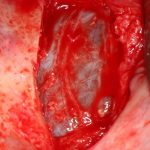

Сначала обнаруживаем и выделяем дефект слизистой так, чтобы он максимально уменьшился:

подбираем барьерную мембрану, подгоняем ее по размеру:

приклеиваем получившуюся «заплатку» и заполняем субантральное пространство графтом: